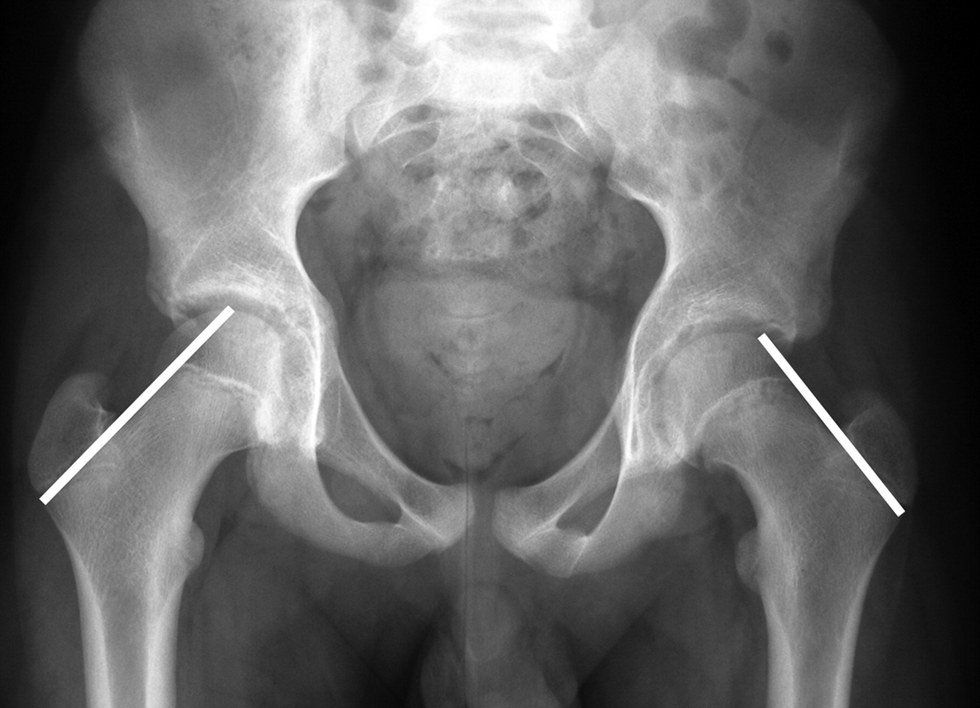

My growth plate, which was supposed to sit on top of my femur, was slipping fast. This incredibly rare genetic phenomenon is known as Slipped Capital Femoral Epiphysis, or SCFE for short. This condition is so rare that there are around two to 10 cases per every 100,000 kids. I would be one of the only cases in the entire state of New Jersey that year, and as a result, I'd be in a bunch of medical journals, because the case has almost never existed in white females of a healthy weight.

I was soon wheeled into emergency surgery. A long procedure left me with a titanium screw implanted into my hip to reinforce my growing joint. I had an allergic reaction to the pain medication, so I was forced to endure the recovery period popping your everyday Advil. The pain scared me, I'll admit it. But the fact that I would be out of all physical activity for at least the following year kept me up at night. I had been playing soccer and lacrosse since I could walk. Who was I without the game?